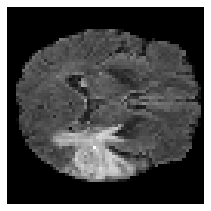

Disentangled representations can be useful in many downstream tasks, help to make deep learning models more interpretable, and allow for control over features of synthetically generated images that can be useful in training other models that require a large number of labelled or unlabelled data. Recently, flow-based generative models have been proposed to generate realistic images by directly modeling the data distribution with invertible functions. In this work, we propose a new flow-based generative model framework, named GLOWin, that is end-to-end invertible and able to learn disentangled representations. Feature disentanglement is achieved by factorizing the latent space into components such that each component learns the representation for one generative factor. Comprehensive experiments have been conducted to evaluate the proposed method on a public brain tumor MR dataset. Quantitative and qualitative results suggest that the proposed method is effective in disentangling the features from complex medical images.